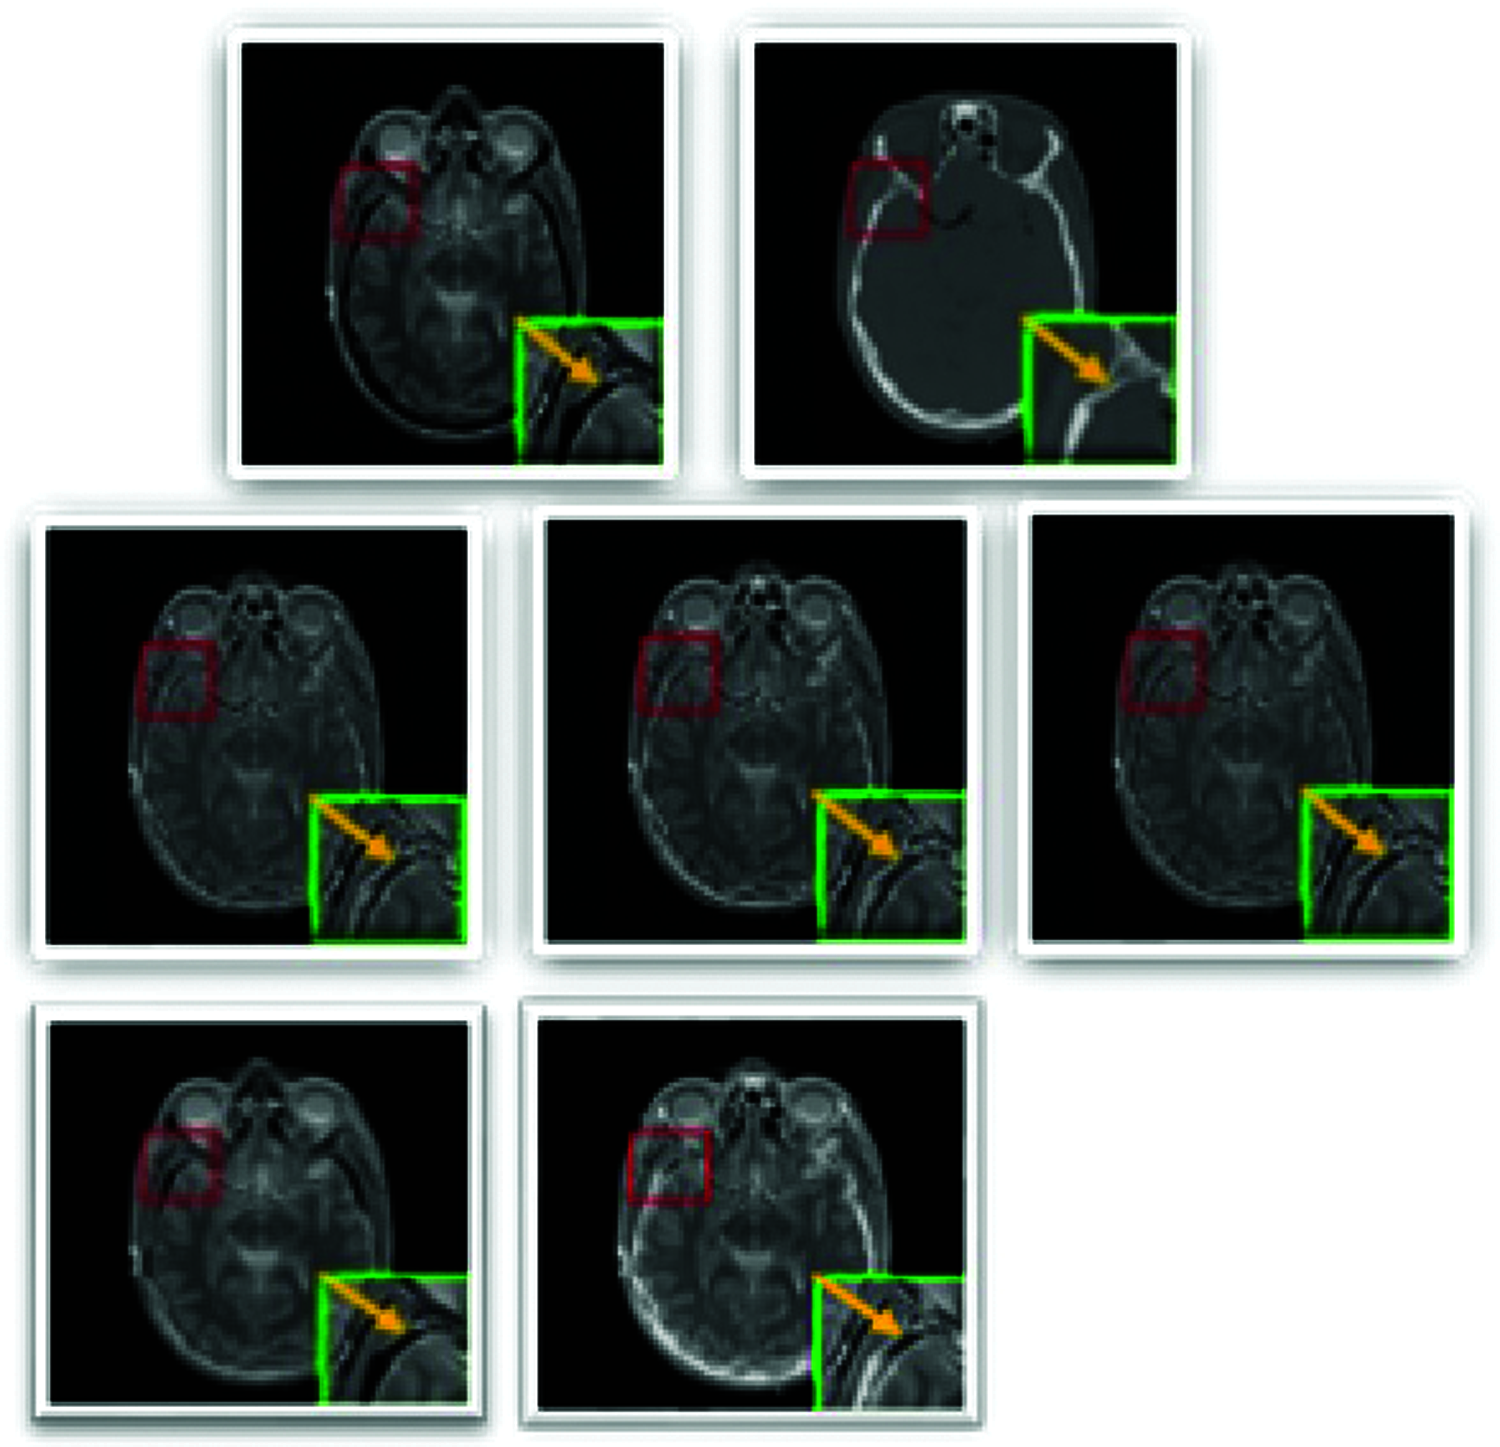

Figure 9: The medical image fusion

4.3 Multi-Modal Medical Image Fusion

CT and MR scanned images of the human brain are collected together. The fused image should have more skull information from the CT and textural tissue properties from MR. Fig. 9, the first row is the input images MR, CT scan images, respectively (From left to right). The second row is the fused images of the first row images. Mean, Max, and the sum is the Fusion rule applied during the fusion process (from left to right). The image part framed by a green box in each subfigure denotes the image part's close-up marked by a red box. The third row is output images of GF_IF and MSTSR_IF.

The experimental results are in Tab. 5.

Tab. 5 also concludes that for Medical IF also IF_Max gives the best response. Tab. 5 chart is in Fig. 10.

Fig. 10 shows that IF_Max is the best suitable IF method over CT and MRI images.